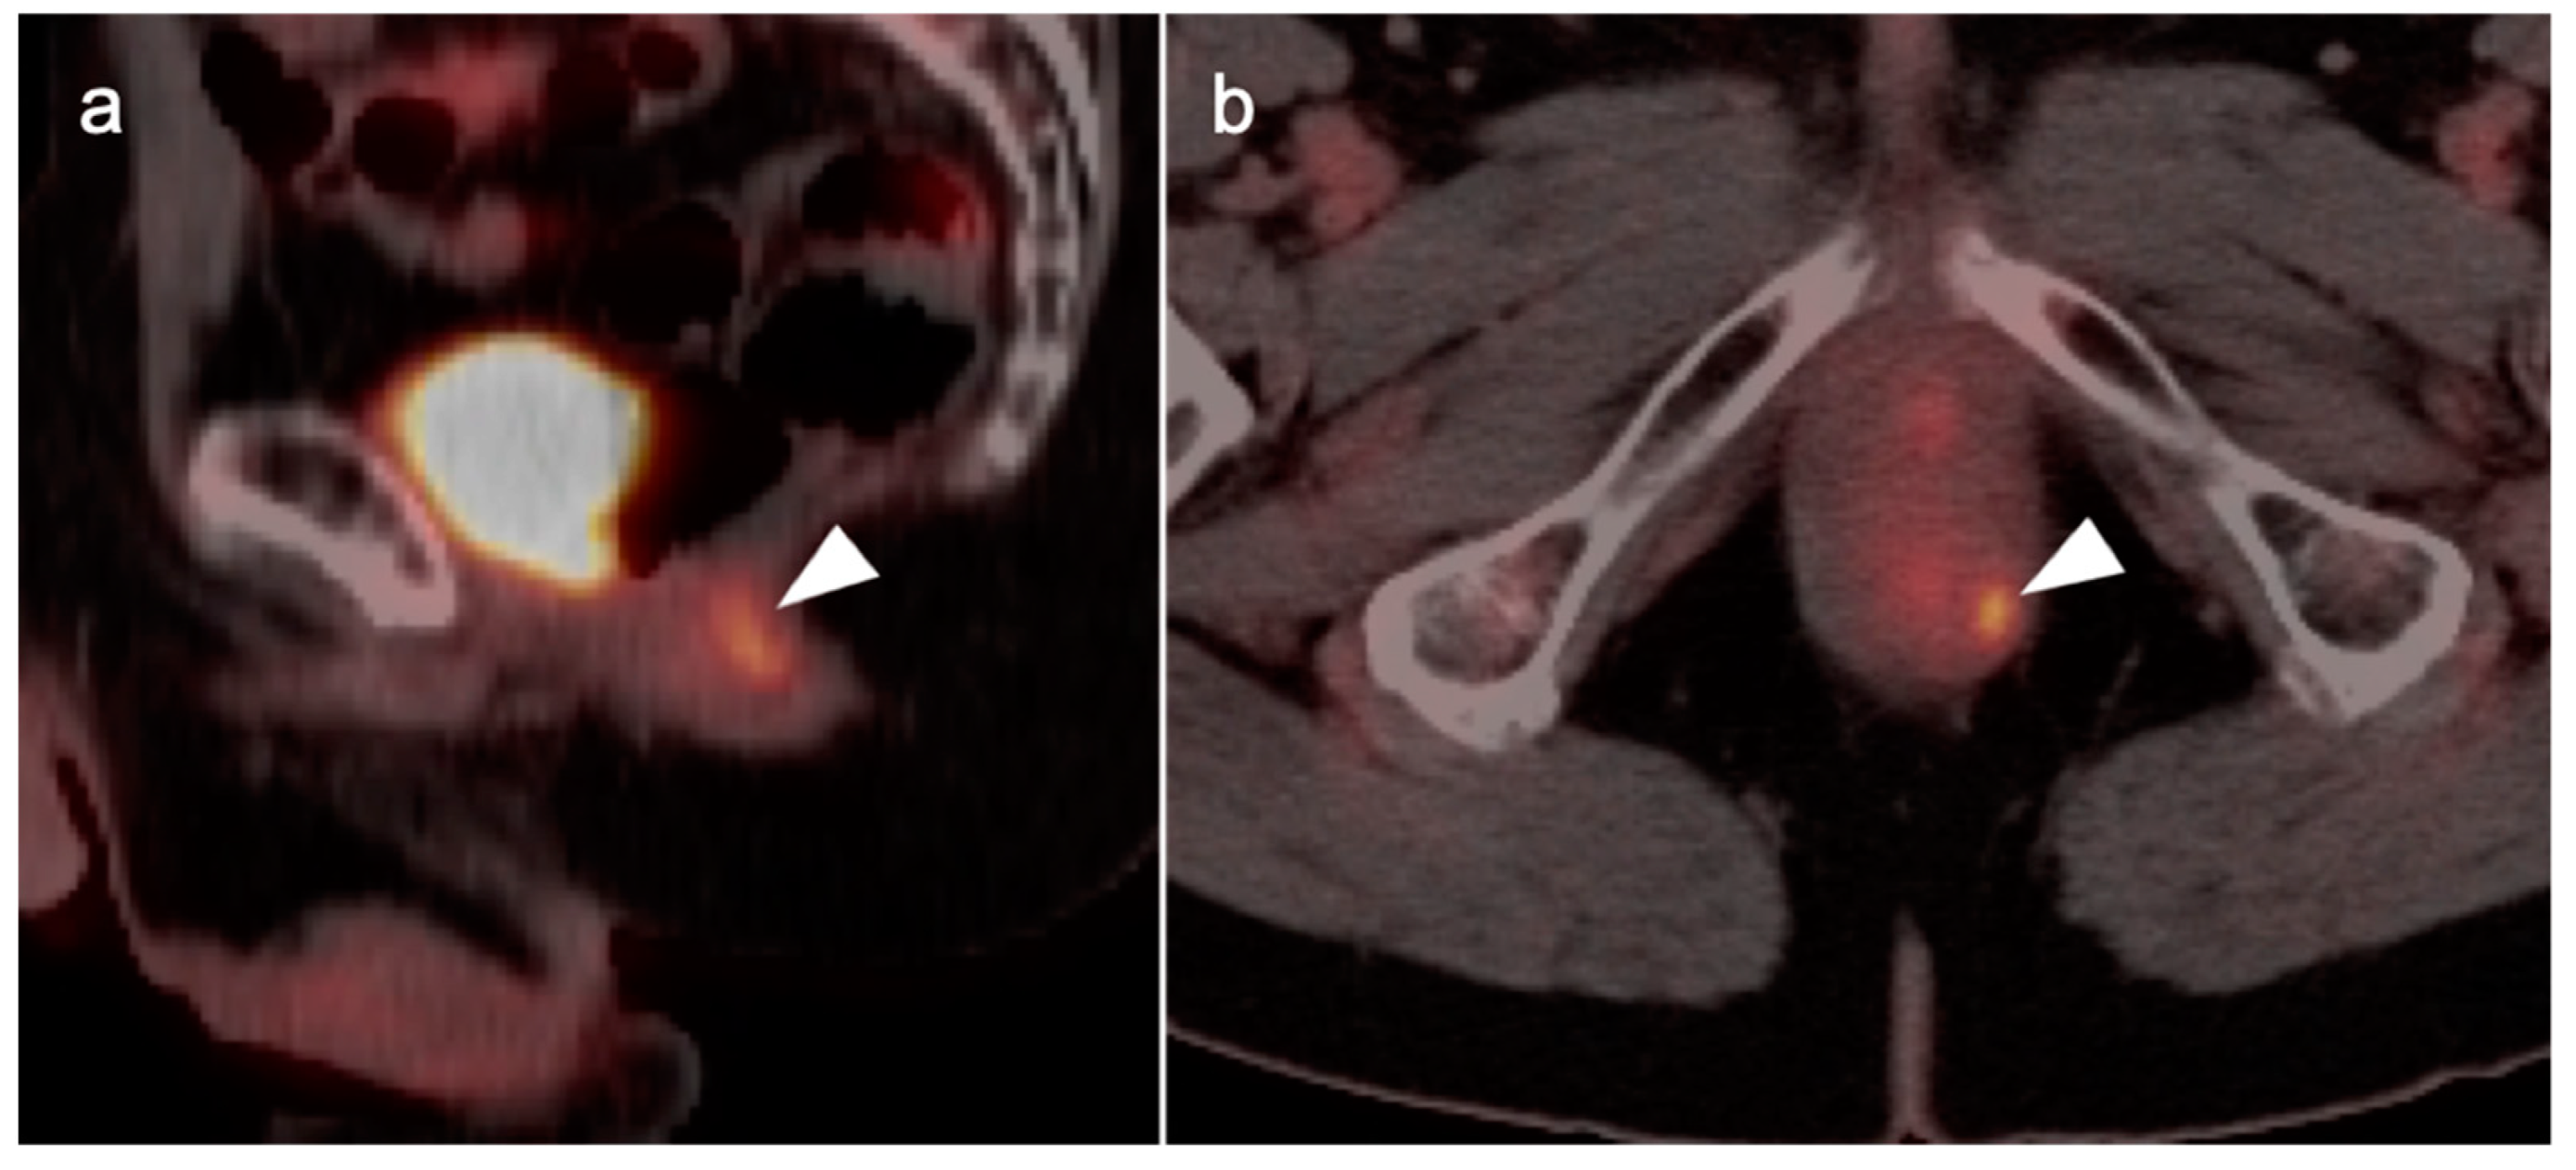

10. Anal Carcinoma